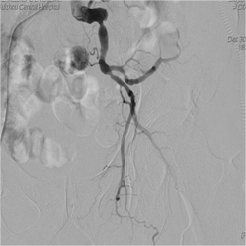

医院检查双下肢动脉CTA示:腹主动脉下段、双侧髂总动脉、双侧髂内动脉及右侧髂外动脉多发粥样硬化;左侧髂外动脉、双侧股浅动脉及左胫前动脉闭塞。